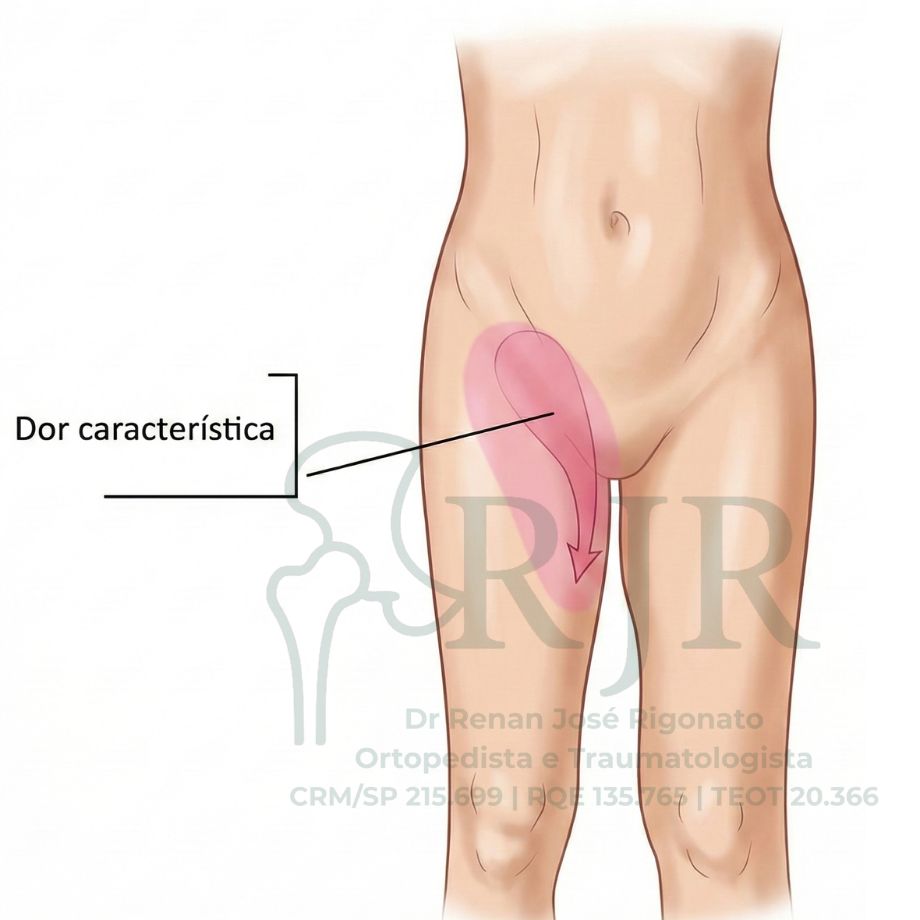

Os sintomas da osteonecrose da cabeça do fêmur variam conforme a evolução da doença e estão diretamente relacionados ao comprometimento estrutural do osso. A progressão do quadro leva à perda do formato normal da cabeça do fêmur e ao desenvolvimento de artrose secundária do quadril, o que explica a piora clínica.

- Fase marcada pela dor no quadril, geralmente localizada na virilha e coxa

- Dor normalmente contínua, podendo vir no repouso e durante o sono